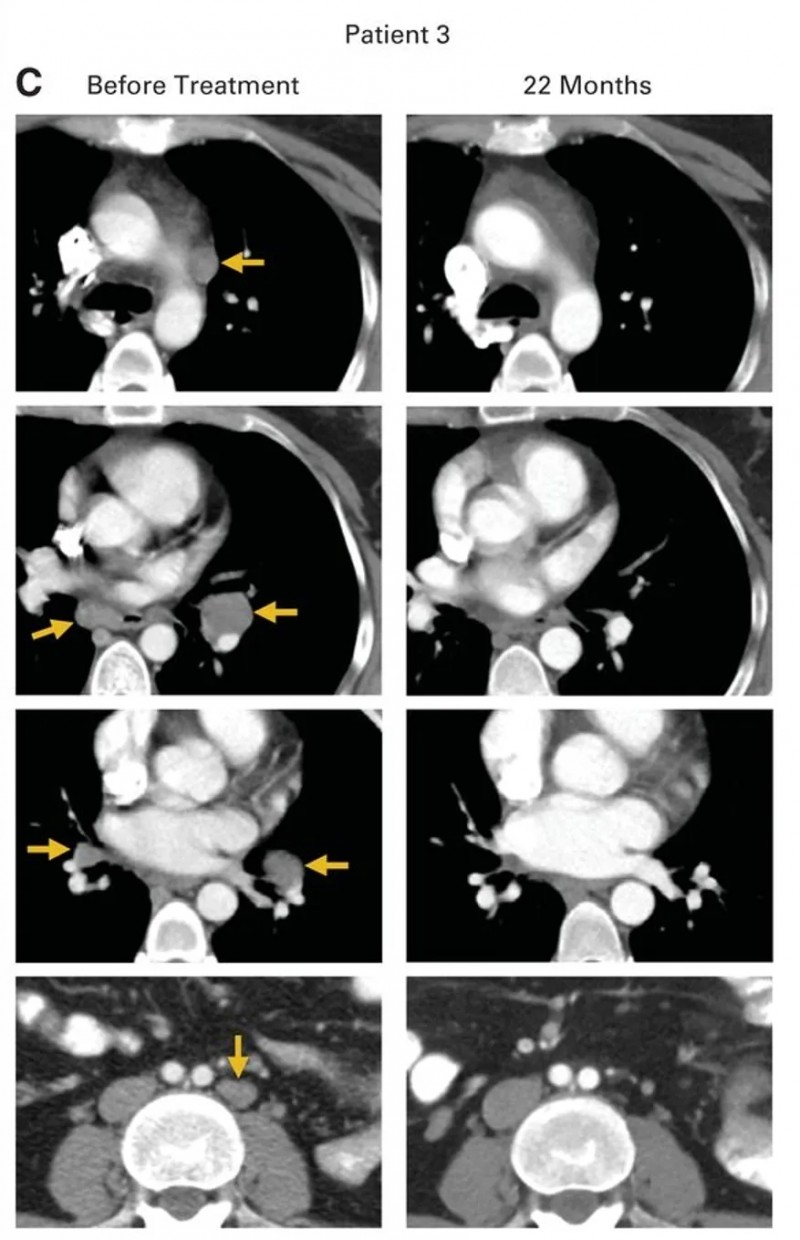

患者3

患者3是一位患有转移性鳞状细胞癌的女性,此前接受过多线治疗,包括顺铂+长春新碱+博来霉素诱导化疗、吉西他滨+顺铂放化疗,后续出现气管旁、隆突下及双侧肺门淋巴结转移,经拓扑替康+紫杉醇治疗后病情仍进展,治疗时肿瘤已转移至腹主动脉旁、双侧肺门、隆突下及髂淋巴结。接受HPV-TIL治疗后,所有病灶完全消退(详见下图A、C),治疗后22个月无疾病复发。

▲图源“JCO”,版权归原作者所有,如无意中侵犯了知识产权,请联系我们删除